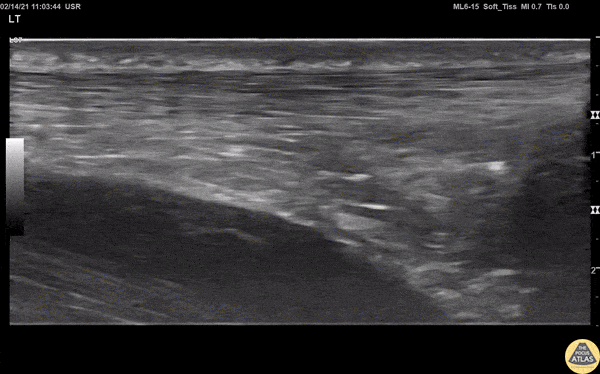

View of a normal Achilles tendon as seen in long axis, using a linear transducer. The relatively hyperechoic, linear fibers of the tendon are seen running from the calcaneus (right of screen, or inferior) to the gastrocnemius muscle (off screen to the left, or superior).